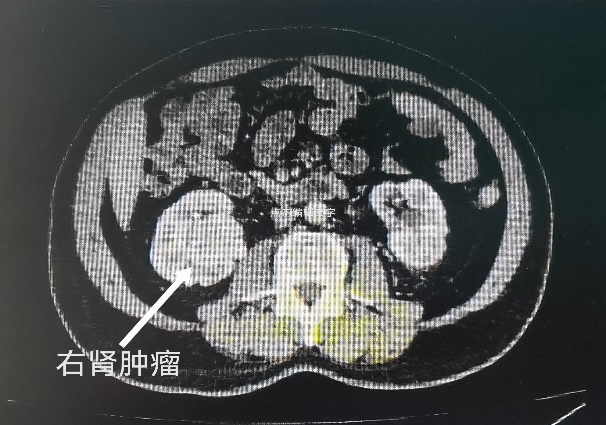

入院后,经过全方面检查与多次会诊,在同患者进行深入沟通后,张奇夫教授决定为李大爷进行保留肾脏的手术。张奇夫教授表示,临床上对于肾癌常用的手术方式有两种:一种是单纯切除肿瘤,保留正常肾组织;另一种是根治性肾切除手术,将整个肾和肿瘤一起切除。李大爷患有双侧肾癌,如果根治性双肾切除,对于医生来讲,手术就没有什么特殊难度了,但是对于李大爷来讲,终生的透析不仅是经济负担,更是严重影响生活质量。他的双肾肿瘤体积均超过了4厘米,并且右肾肿瘤属于肾内型,长在肾脏的中央,肿瘤紧邻肾脏集合系统与肾脏血管,手术风险和难度太大,患者左肾既往做过结石手术,肾脏周围瘢痕黏连较重,左肾形态已经有所改变,手术也存在不确定性。但考虑到患者强烈的保留肾脏意愿,行“肾部分切除术”是最佳选择。同时,他判断,该患者双侧肾脏不宜同时手术,那样对肾脏打击太大,容易出现肾功能衰竭。综合病情,左侧肾脏切除肿瘤保留肾脏的成功率较大,因此决定先行左侧肾脏的保肾手术。

经过充分的术前准备,2022年10月,张奇夫教授团队为李大爷进行了左肾部分切除术。术中情况正如术前预料的一样,因患者左肾既往做过结石手术,肾脏周围黏连明显,手术难度较大。但在团队的通力配合下,还是顺利完成了手术。术后的病理检查结果是透明细胞癌,也证实了术前的诊断。术后经过精心的护理和治疗,李大爷恢复的很好,顺利出院修养,为第二次右肾的手术做好准备,医生们对于接下来的治疗也充满了信心。

2023年1月,李大爷返回医院准备第二次手术。然而术前的检查结果并不是非常理想,虽然右肾的肿瘤体积没有明显增大,抽血化验肾功能也没发现明显异常,但是通过肾动态显像检查发现,李大爷的两侧肾脏功能都不理想。左肾因为经过结石和肿瘤两次手术,左肾功能还不到正常的二分之一,右侧肾脏因为肿瘤的影响,功能也处于较低水平。如果接下来的手术没有保留住右侧肾脏将右侧肾脏切除,术后极大可能会出现肾功能衰竭,需要透析治疗。面对这种情况,医生们也感到了很大压力,经过全面的术前检查与病情评估,考虑到术中各种情况与细节,并经过麻醉科会诊,张奇夫教授带领团队医生下定决心,一定要保住李大爷的右肾。

这次手术既是对外科医生技术的考验也是对心理素质的考验,手术操作要非常精细,既要切除肿瘤,又要尽可能多的保留正常肾组织,稍有不慎就可能伤及肾脏动脉导致大出血,那样最终只能将右肾切除。术中,张奇夫教授凭借丰富的经验及精湛的技术,剖开肾脏,将位于肾脏中央的肿瘤完整的剥离出来,成功为患者保住了右侧近90%肾组织,整个肾脏的阻断缺血时间只有26分钟,最大可能的减少了手术对肾脏功能的影响。保留肾脏的肿瘤切除手术就是与时间赛跑,因为在行肿瘤切除时需阻断肾脏的血流,要争取在最短时间内完成手术,以免肾脏功能因长时间缺血导致不可逆的损伤,术中还采用了肾脏表面低温技术,更有利于降低肾脏功能受损的风险。